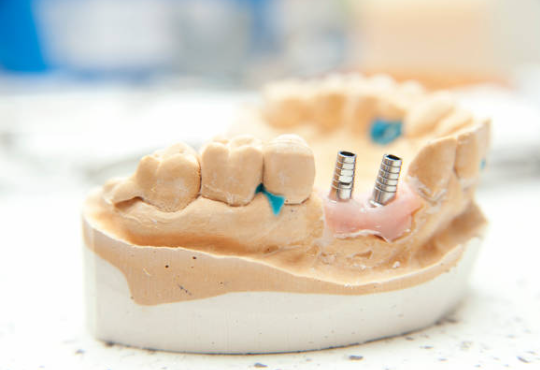

임플란트는 크게 세 부분으로 나뉘며, 치아 뿌리를 대신하는 구조물인 임플란트 (인공치근), 그 위에 체결을 하는 보철기둥 (지대주), 마지막으로 그 위에 씌우는 보철물 (크라운)이 있습니다.